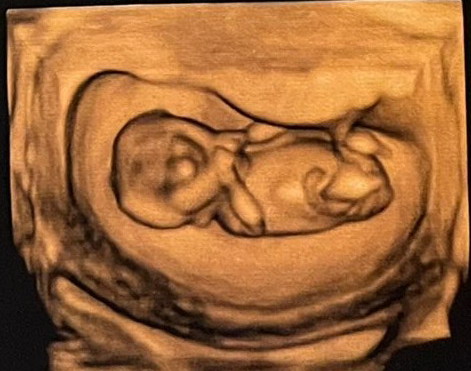

Pierwsze zdjęcia małej Lidzi

Miała być Duszana, ale wyszło, że będzie Lidia Małgorzata. Teraz ma 5 centymetrów i, jako niezależy obiekt żywy, będzie z nami pod koniec czerwca 2026 roku. Wtedy dołączy do nas kolejny kochany obiekt zbudowany na podstawie samolubnych genów, w pewnej części i moich. Trzy miesiące temu rozpoczął się naturalny proces samobudowania się tego obiektu.